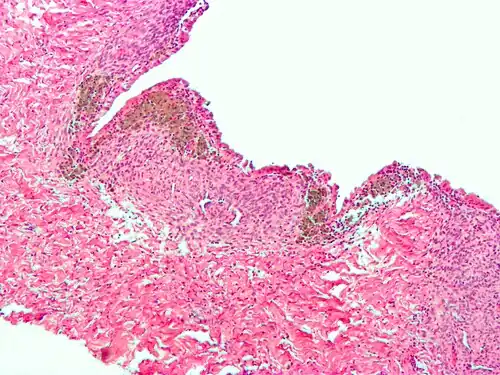

A biopsy may be negative even when endometriosis is present, particularly in younger women. As such, it cannot be used to exclude a diagnosis of endometriosis.[8] For confirmation, biopsy samples should show at least two of the following features:[38]

- Endometrial type stroma

- Endometrial epithelium with glands

- Evidence of chronic hemorrhage, such as hemosiderin deposits

-

Endometriosis, abdominal wall -

Micrograph of the wall of an endometrioma. All features of endometriosis are present (endometrial glands, endometrial stroma and hemosiderin-laden macrophages)